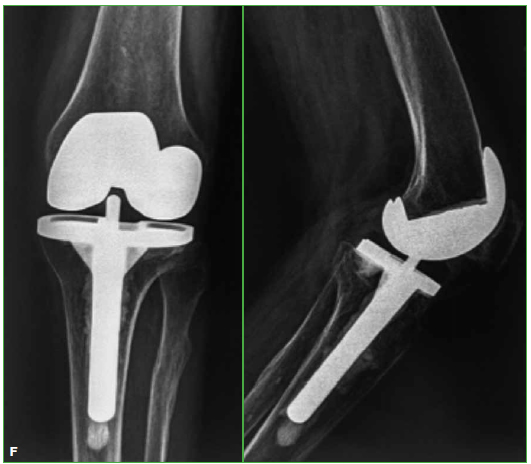

Materiales y Métodos: Estudio retrospectivo observacional, entre mayo de 1999 y enero de 2013. Se evaluaron 25 RTR en 24 pacientes (edad promedio 67.1 años) con secuela de fractura articular de rodilla y un seguimiento promedio de 6.1 años. Tres (12%) tenían cirugías anteriores al RTR. Ocho se resolvieron en dos tiempos. Se empleó un implante constreñido en 4 pacientes (16%). Se determinaron el KSS, el KSSf y el rango de movilidad preoperatorios y del último control. Se documentó la supervivencia del implante.

Resultados: El KSS se incrementó de 38,5 en el preoperatorio a 82,8 en promedio. El KSSf posoperatorio mejoró de 48 a 85. El rango de movilidad aumentó de un promedio de 7,5-76° a 1-102,4° en el posoperatorio. Cuatro casos fueron reoperados. La supervivencia de la prótesis fue del 92% a los 6.1 años.

Conclusiones: El RTR es adecuado para la gonartrosis postraumática en su estadio final, con buenos resultados a mediano plazo. Si se logran una adecuada alineación posoperatoria y un correcto posicionamiento de los componentes, los resultados son satisfactorios y se asemejan a los del RTR por gonartrosis idiopática.